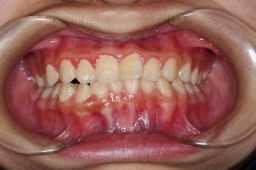

私の娘:掛園 綾です。2002年01月19日生 2007年03月19日(5才2ヶ月) 骨格性反対咬合(C〜C) 矯正用の床装置を作っても寝ると すぐ自然に吐き出す。また床装置を入れると 寝れないと主張。 |